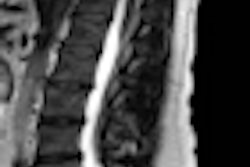

The U.S. Centers for Medicare and Medicaid Services (CMS) has revised its policy on reimbursement for the use of MRI in patients with pacemakers to support coverage of the exams in clinical studies.

Previously, CMS did not cover payment for an MRI examination for patients with cardiac pacemakers. The FDA has decided to continue that policy for most Medicare beneficiaries; it stated that it is not convinced that the use of MRI improves health outcomes for patients with implanted permanent pacemakers (PMs) or implantable cardioverter defibrillators (ICDs).

However, the agency has proposed that MRI be reimbursed by CMS for patients participating in some clinical studies. To receive reimbursement, these studies must address whether the devices affect physician decision-making or affect patient outcomes. In addition, studies must include safety criteria for all patients.

In the document announcing the new policy, CMS stated that the agency believes the evidence is "promising" -- although not yet convincing -- that MRI will improve patient health outcomes "if certain safeguards are in place to ensure that the exposure of the device to an MRI environment adversely affects neither the interpretation of the MRI result nor the proper functioning of the implanted device itself."